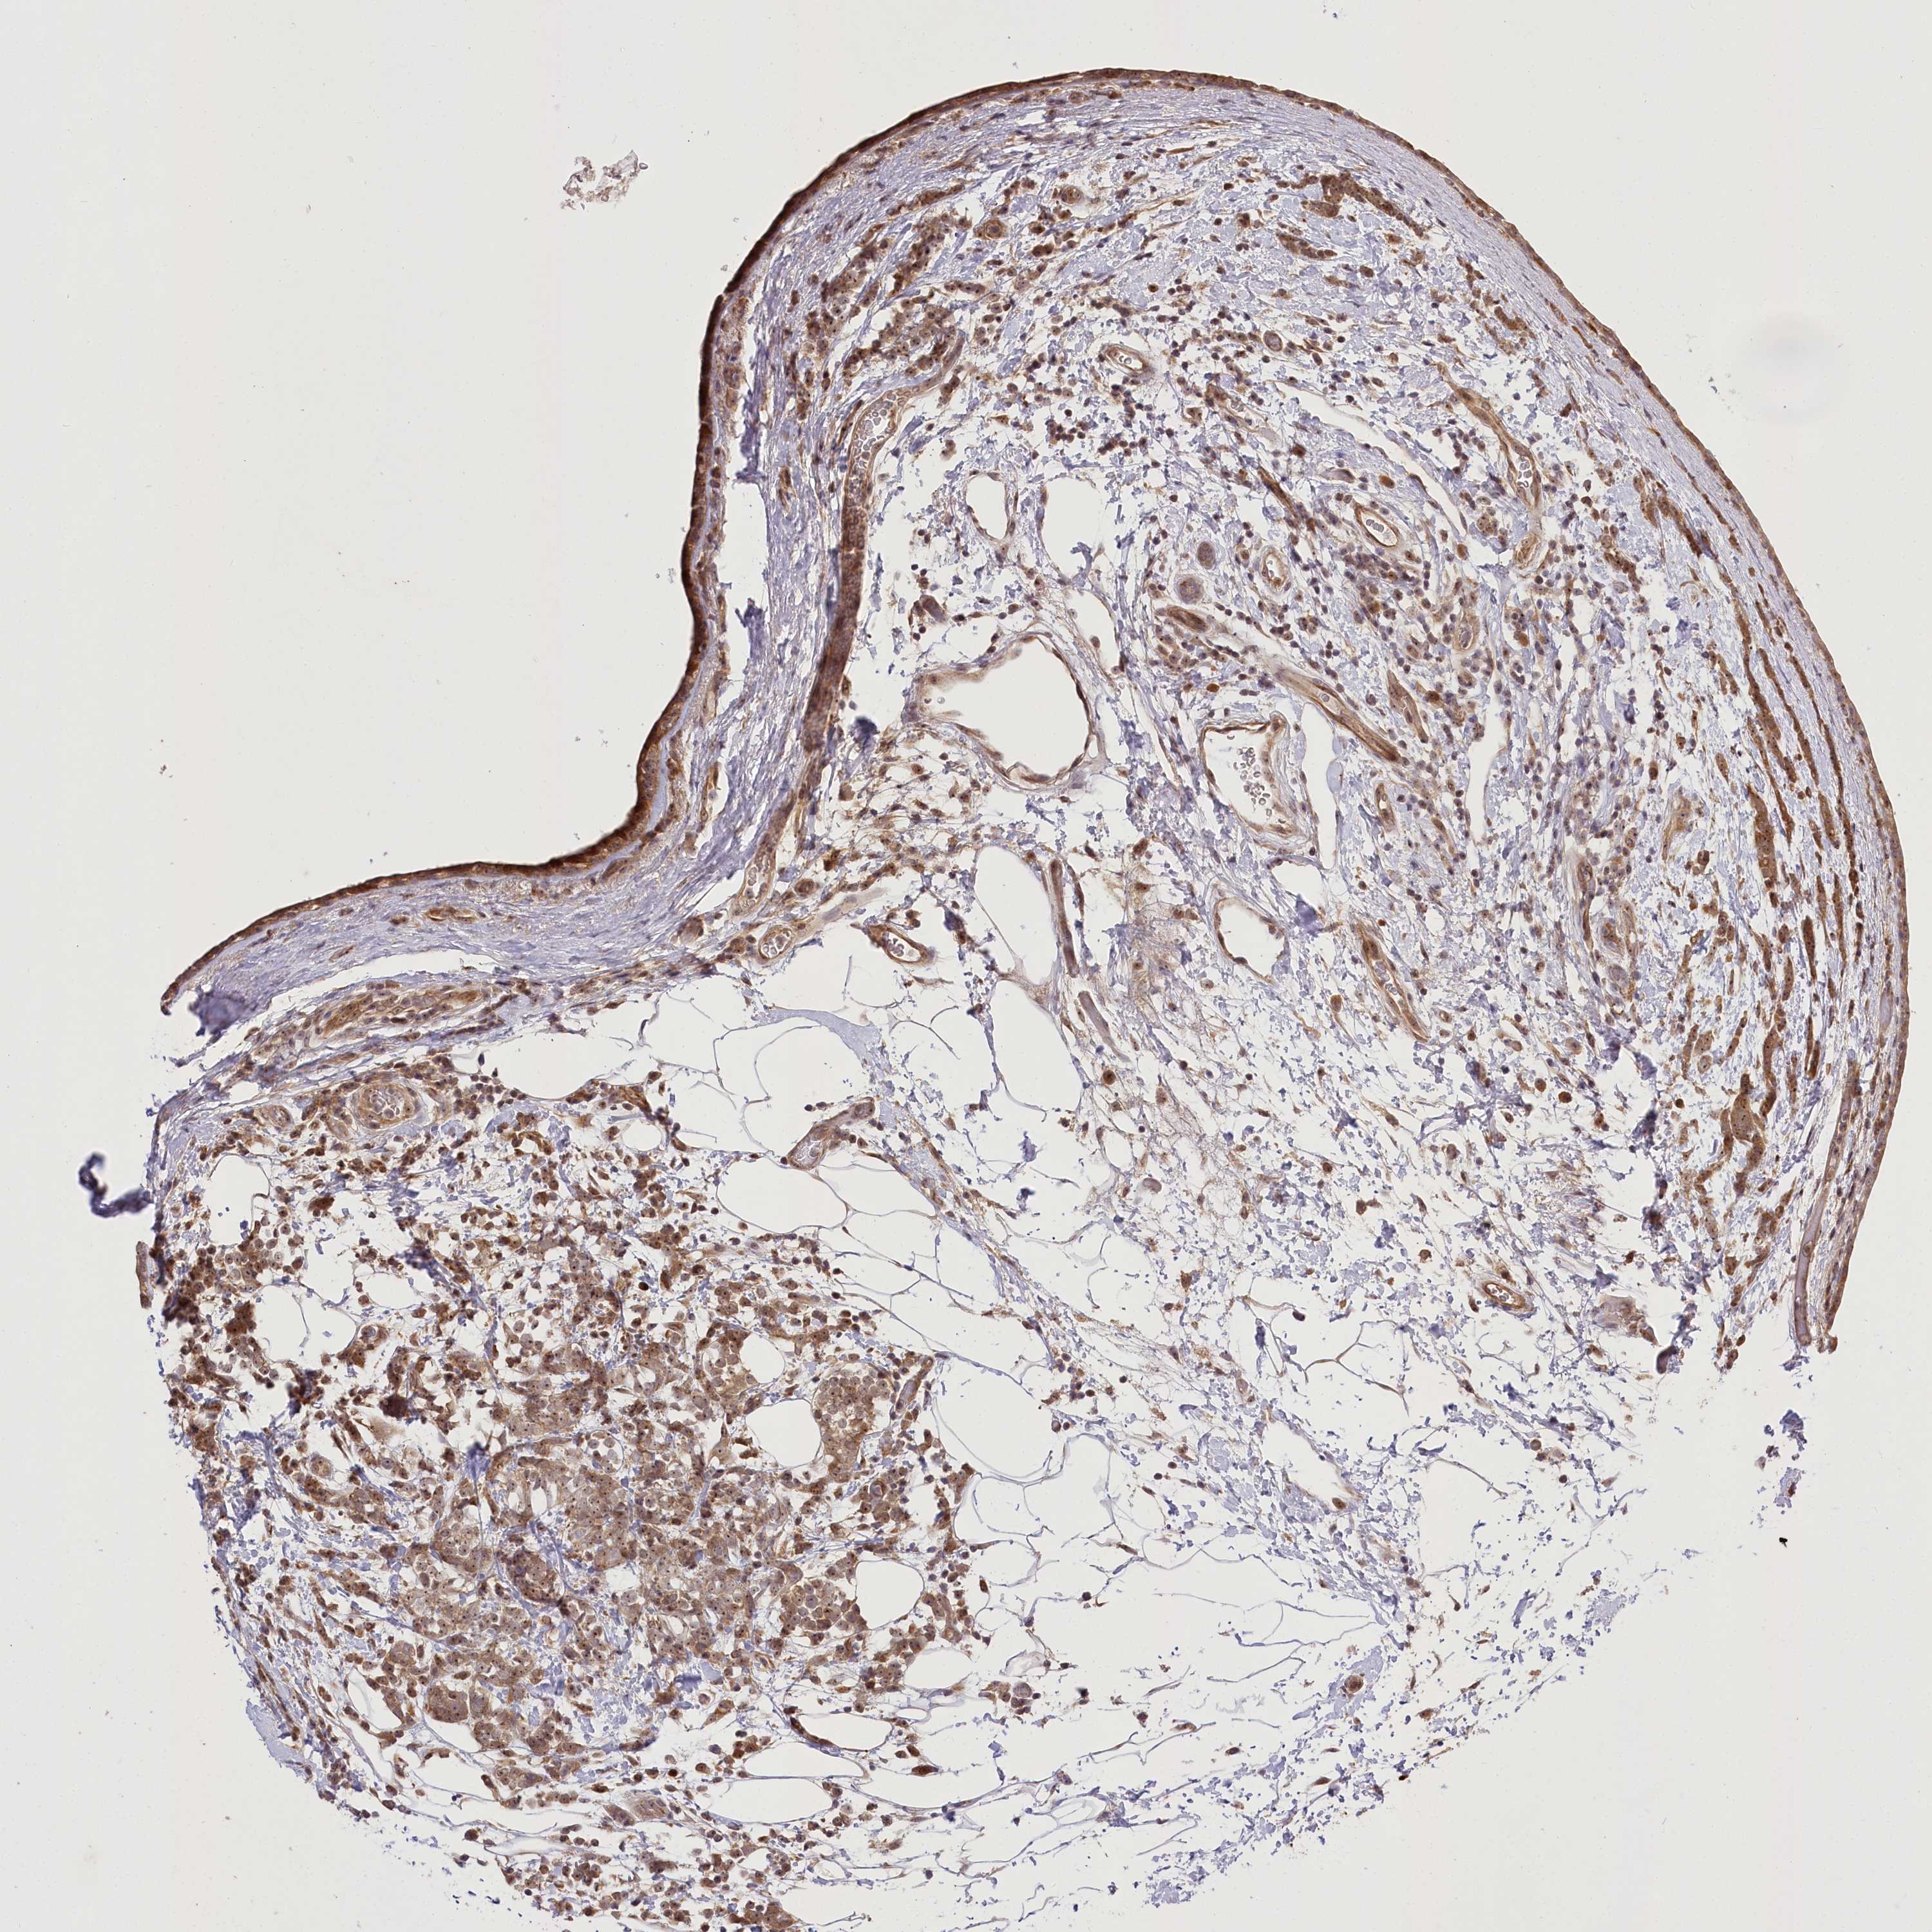

CANCER BREAST CANCER Show tissue menu

BRCA TCGA BRCA VALIDATION PROTEIN EXPRESSION